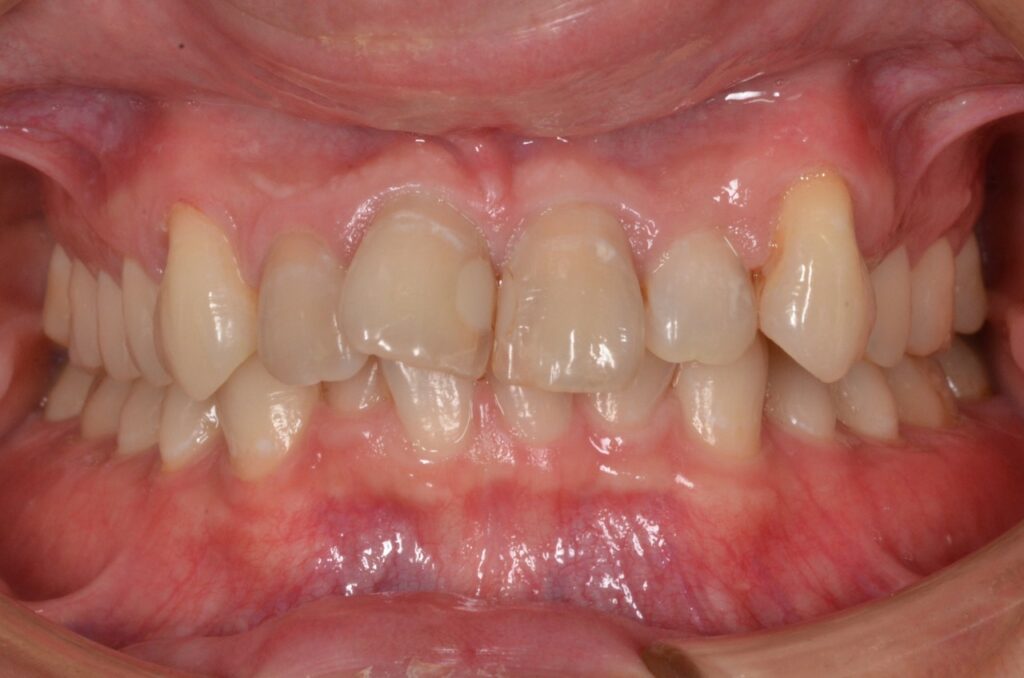

特に前歯に叢生が見受けられます。ワイヤー矯正であれば半年から一年で治療終了できそうですが、患者様のご要望でマウスピース治療となりました。

また、前歯4本は色も濃くプラスチックで補綴されていることもありセラミック治療となりました。